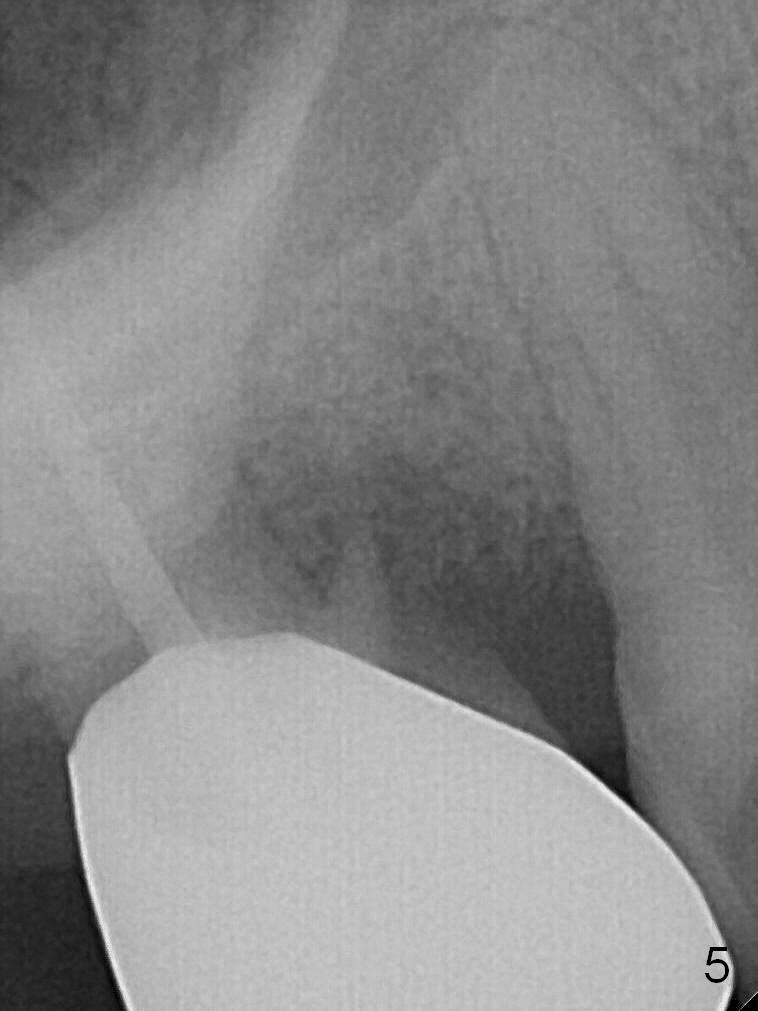

A 56-year-old man has discomfort associated with the tooth #3 one year and a half after root canal therapy (Fig.1: mesiobuccal root vertical fracture). Since an implant is just placed at #19 and another one will be encouraged to be placed at #2 (Fig.2), root amputation may be a valid treatment modality (Fig.3,4). After debridement and Clindamycin topical application, allograft/Osteogen is placed (Fig.5,6 (dashed line)), followed by Osteogen plug (Fig.7 *). Discomfort apparently shifts to the distobuccal root 9 months postop, while the MB defect seems to heal (Fig.8 *). Extraction and implant is expected.